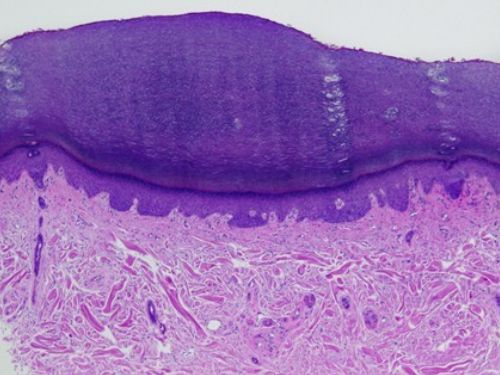

Beschrijving:Normaal aspect van het stratum corneum bij

normale uitrijping van de epidermis. De naam

basket weave

komt van een gevlochten mandje, denk aan een gevlochten broodmandje.

Meer informatie:Een normaal verhoornende hoornlaag

heet

orthokeratose, een normale hoornlaag met een

basketweave patroon noemt men

basket-weave orthokeratose.

Op de handpalmen en voetzolen is er normaal sprake van compacte orthokeratose.

Orthokeratose komt voor bij:- normale huid